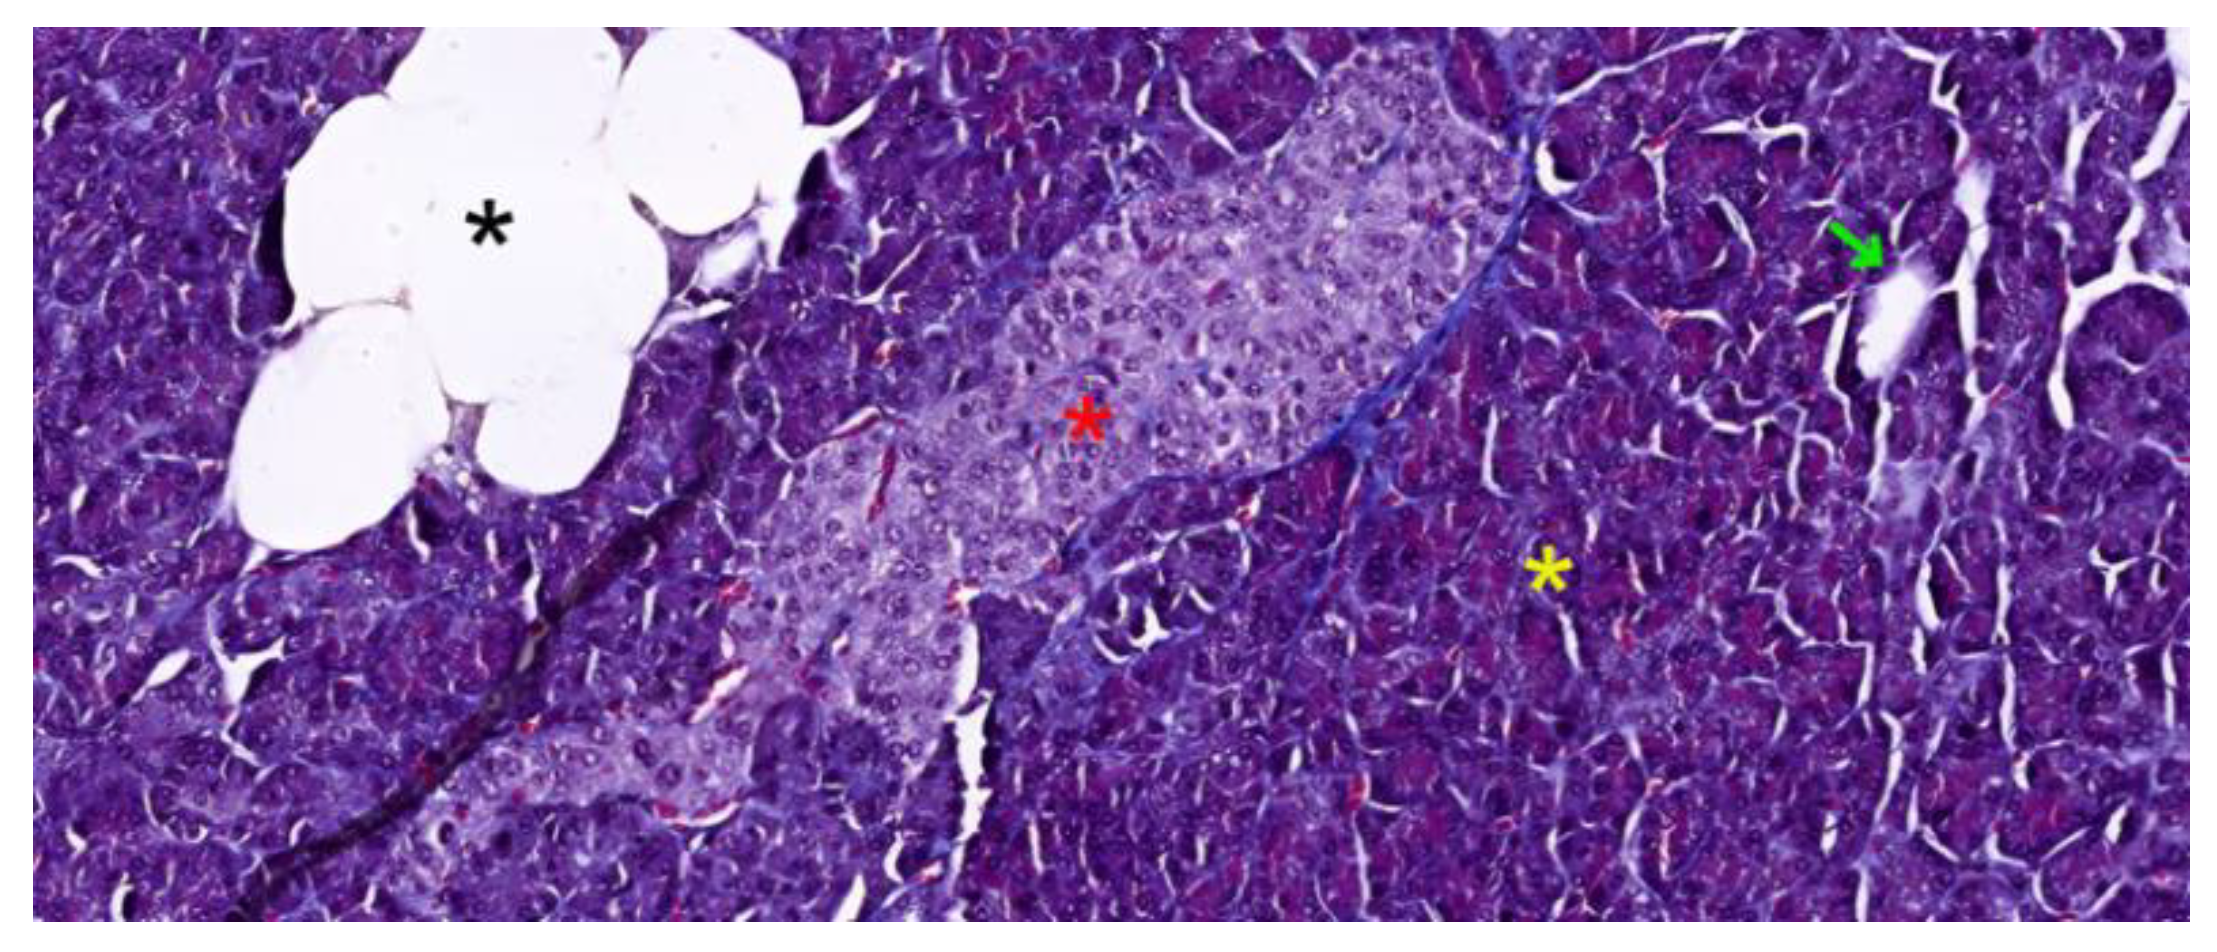

2.2.1. Supporting Connective Tissues

- Intra-lobular ducts - represented by intercalated ducts that continue the lumen of the acini and are delimited by simple cuboidal epithelium; intercalated ducts fuse to form proper intra-lobular ducts, which are larger and delimited by simple cuboidal or columnar epithelium; around these ducts, a loose connective stroma can be observed, with numerous reticulin fibers, yet quantitatively reduced overall; unlike major salivary glands, the exocrine pancreas does not have striated ducts (see Figure 4a/4b);

- Inter-lobular ducts - located in connective trabeculae; they have a wide lumen and are delimited by simple columnar epithelium; they are surrounded by well-represented dense irregular connective tissue, which contains fibroblasts and myofibroblasts (see Figure 5);